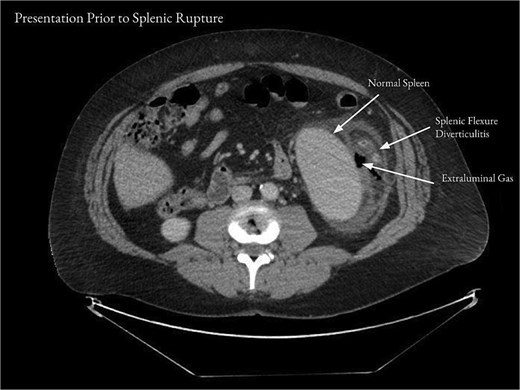

On examination, the patient appeared mildly ill and uncomfortable. Blood pressure was 132/81, heart rate was 107, and temperature was 37.8°C. The abdomen was soft, with moderate left upper quadrant and left flank tenderness, mild distention, and no guarding. Laboratory workup revealed a white blood cell (WBC) count of 13.2 × 103/μl, a hemoglobin of 13.5 g/dl, and a hematocrit 36.0%. Computed tomography (CT) of the abdomen and pelvis with contrast showed acute diverticulitis of the splenic flexure with moderate wall thickening. There was adjacent extraluminal gas consistent with localized perforation (Fig. 1).

Computed tomography of the abdomen and pelvis on presentation showed acute diverticulitis of the splenic flexure with moderate wall thickening and adjacent extraluminal gas consistent with localized perforation.